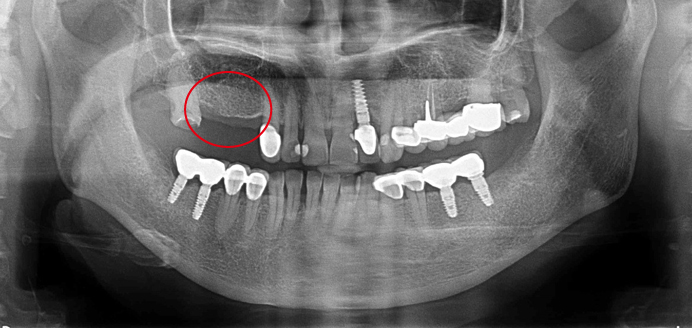

案例介紹 人工植牙 微創手術 施行